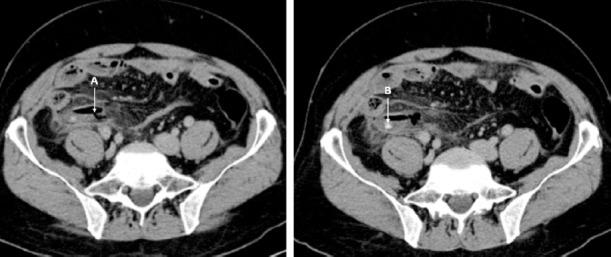

This study included 80 patients, 32 (40%) classified as perforated appendicitis (Group-1) and 48 (60%) as non-perforated appendicitis (Group-2). The C-reactive protein value was found to be statistically higher in Group-1 than in Group-2 (177.5±118.9 and 100.2±87.3 mg / L, respectively; p=0.001). The appendix lumen diameter (p=0.002), appendix wall defect (p<0.001), peritoneal thickening and enhancement (p<0.001), ascites (p=0.031), intra-abdominal abscess (p=0.003), jejunal thickening (p=0.019), ileal thick-ening (p=0.008), and ileus (p=0.035) values were significantly higher in Group-1. In the binominal logistic regression analysis performed with statistically significant data, an appendiceal wall defect (OR: 0.069, 95% CI=0.014-0.327, p=0.001) and peritoneal thickening and enhancement (OR: 0.131, 95% CI=0.024-0.714, p=0.019) were identified as independent variables for perforated appendicitis.

Among CT findings, appendix wall defects and peritoneal thickening and enhancement play an important role in detecting perforation.

本研究包括 80 例患者,32 例(40%)为穿孔性阑尾炎(第 1 组),48 例(60%)为非穿孔性阑尾炎(第 2 组)。第 1 组的 C 反应蛋白值明显高于第 2 组(分别为 177.5±118.9 和 100.2±87.3mg/L;p=0.001)。阑尾腔直径(p=0.002)、阑尾壁缺损(p<0.001)、腹膜增厚和增强(p<0.001)、腹水(p=0.031)、腹腔脓肿(p=0.003)、空肠增厚(p=0.019)、回肠增厚(p=0.008)和肠梗阻(p=0.035)值在第 1 组中明显更高。在进行统计学显著数据的二项逻辑回归分析中,阑尾壁缺损(OR:0.069,95%CI=0.014-0.327,p=0.001)和腹膜增厚和增强(OR:0.131,95%CI=0.024-0.714,p=0.019)被确定为穿孔性阑尾炎的独立变量。

在 CT 发现中,阑尾壁缺损和腹膜增厚和增强在检测穿孔中起着重要作用。